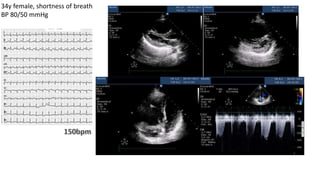

34y female, shortness of breath

BP 80/50 mmHg

Courtesy of Hatem Soliman